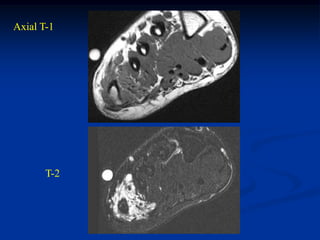

Case #284

Coronal T-1 MRI

49 year male with

well-differentiated

liposarcoma (atypical lipoma)

distal thigh

Sagittal T-1 MRI

Axial T-2 MRI

Case #284 Coronal T-1MRI 49 year male with well-differentiated liposarcoma (atypical lipoma) distal thigh